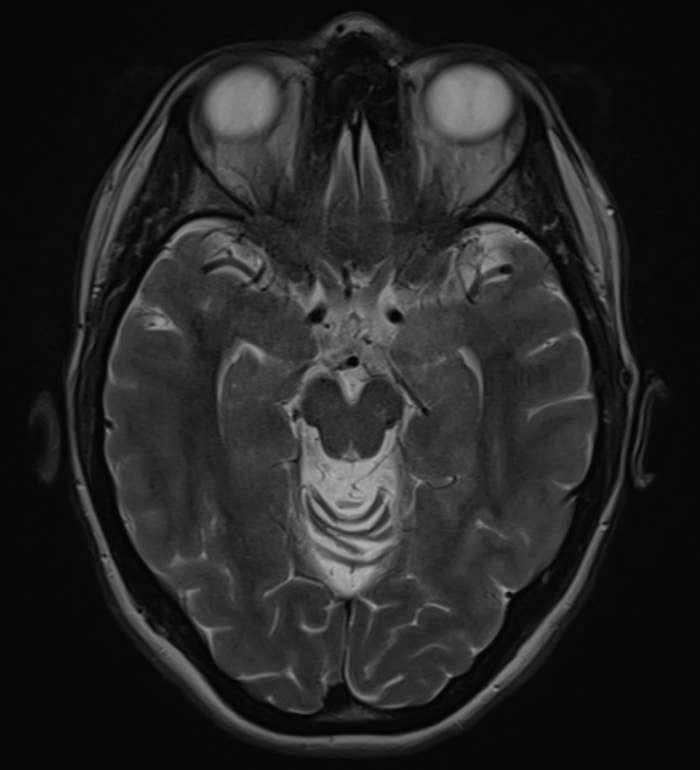

Neurologists Are Opening Up About Sleep Problems That Might Be Warning Signs Of Dementia

Experts reveal which sleep disturbances may signal something deeper, and when you should be concerned. This article originally appeared on HuffPost.